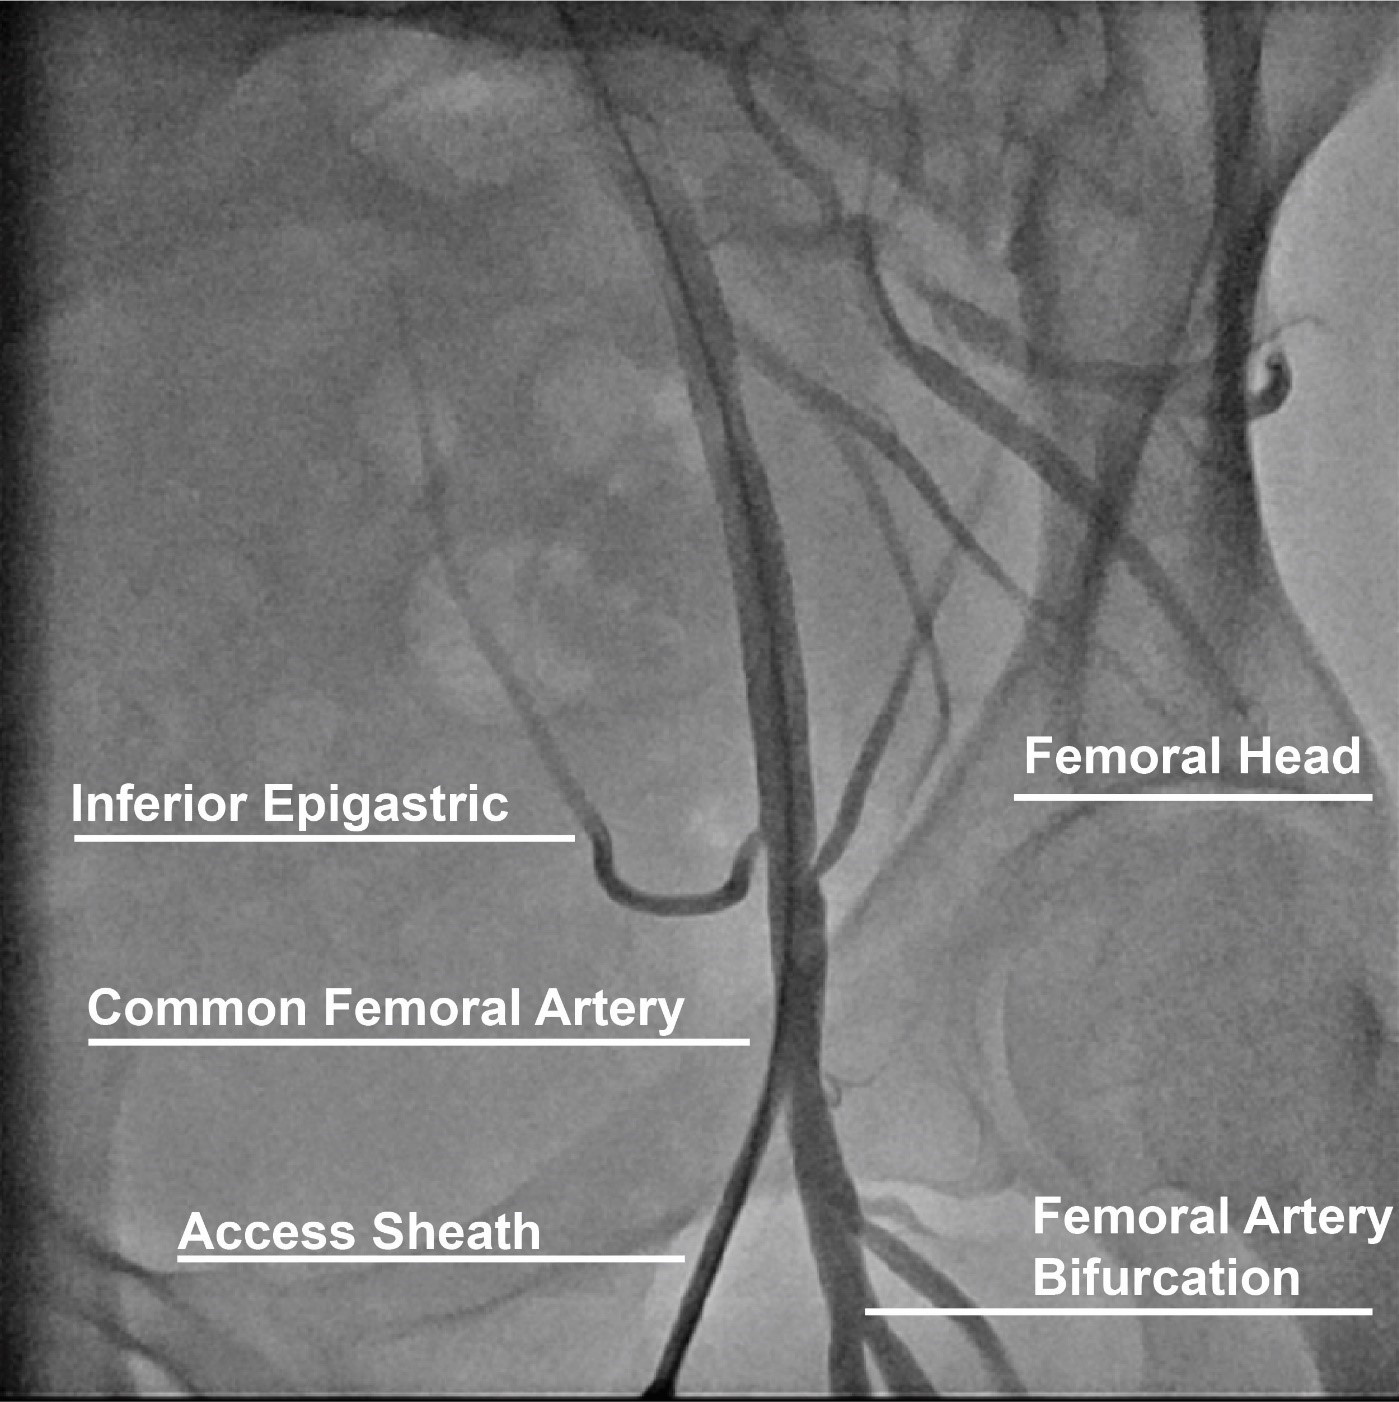

Contemporary femoral access should utilize all available techniques and adjunctive information available to reproducibly achieve vascular access with the lowest complication rate possible [18]. With the patient supine on the catheterization table, anatomic landmarks should be assessed. In patients with a large body mass index, retraction of the pannus can facilitate vascular access as well as hemostasis and closure. Placement of a radiopaque marker (hemostat) should be utilized in conjunction with fluoroscopy to assess the lower edge of the femoral head (Fig. 2). This location can be marked with a sterile pen and may help avoid high puncture. Ultrasound should then be performed to assess the ideal entry point for CFA access. The ultrasound probe can initially be placed perpendicular to the patient at the location of the lower edge of the femoral head as previously identified. Prior to attempting access the operator should assess the femoral artery anatomy including the location of the CFA bifurcation into SFA and PFA and evaluate for any major branch vessel, areas with severe calcification or obstructive peripheral arterial disease that should be avoided (Figs. 3,4). Longitudinal assessment of the CFA as it dives into the pelvis can also help the operator avoid high access, as well as visualization of the femoral head. Once the ideal target area of vascular access has been located with the ultrasound probe, careful attention should be given to any manipulation of the ultrasound probe. The ultrasound probe should be static and maintained straight without any tilting or angulation. Skin puncture with the access needle should occur 1–2 cm distal to the probe while aligned with the center marker on the probe and approximately 30–45 degrees. Steep angulations should be avoided as they can contribute to sheath or wire kinking. Following needle entry into the CFA, a J-tipped or micropuncture wire is introduced. Routine fluoroscopic assessment of needle entry location with the J-tipped/micropuncture wire in place (Fig. 2) should be performed to confirm that the needle entry is over the femoral head. If the needle entry is below or above the femoral head, this safety step allows for removal of the needle to reattempt access. If the needle entry site is satisfactory, then the wire can be advanced, however, tracking of the access wire should be pursued fluoroscopically when using the micropuncture wire as it can enter side-branches such as the inferior epigastric or deep circumflex iliac branches and cause perforations [28]. Following sheath insertion, femoral artery angiography [usually 30 degrees right anterior oblique (RAO) for right CFA access and 30 degrees for left CFA access] should be obtained to confirm safe access without complications, as well as help evaluate the anatomy and assess for tortuosity or peripheral arterial disease (Fig. 2). Occasionally additional angiographic projections may be required to confirm entry site. While femoral angiography can be performed through the micropuncture sheath, the latter provides limited opacification and has the risk for complications such as vessel dissection given that the injection is performed without assessment of hemodynamic waveform and the microcatheter sheath may be positioned against the vessel wall. Therefore, our suggested approach is that femoral angiography should preferably occur with the J-wire in place as such deflects the sheath from the vessel wall and maintains vessel control should complications occur. C-arm rotation can also be utilized to facilitate needle entry visualization. A standard setup for contemporary femoral access is shown in Fig. 5.

Fig. 2.Contemporary femoral access techniques. (A) Placement of hemostat to mark lower edge of femoral head. (B) Fluoroscopy of hemostat. (C,D) Ultrasound of CFA. (E,F) Needle placement and fluoroscopy of needle entry into CFA. (G,H) Placement of 6 french sheath and femoral angiogram to confirm anatomical location, note presence of wire in sheath.